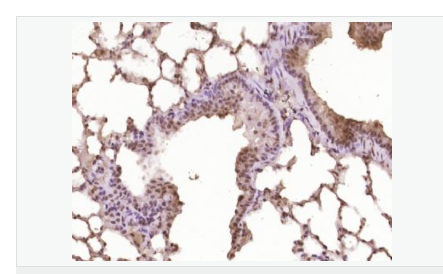

| 產(chǎn)品應(yīng)用 | WB=1:500-2000 ELISA=1:5000-10000 IHC-P=1:100-500 IHC-F=1:100-500 Flow-Cyt=1ug/Test ICC=1:100-500 IF=1:100-500 (石蠟切片需做抗原修復(fù)) not yet tested in other applications. optimal dilutions/concentrations should be determined by the end user. |

| 產(chǎn)品介紹 | This gene encodes a member of the Notch family. Members of this Type 1 transmembrane protein family share structural characteristics including an extracellular domain consisting of multiple epidermal growth factor-like (EGF) repeats, and an intracellular domain consisting of multiple, different domain types. Notch family members play a role in a variety of developmental processes by controlling cell fate decisions. The Notch signaling network is an evolutionarily conserved intercellular signaling pathway which regulates interactions between physically adjacent cells. In Drosophilia, notch interaction with its cell-bound ligands (delta, serrate) establishes an intercellular signaling pathway that plays a key role in development. Homologues of the notch-ligands have also been identified in human, but precise interactions between these ligands and the human notch homologues remain to be determined. This protein is cleaved in the trans-Golgi network, and presented on the cell surface as a heterodimer. This protein functions as a receptor for membrane bound ligands, and may play multiple roles during development. [provided by RefSeq, Jul 2008]. Function: Notch family members play a role in a variety of developmental processes by controlling cell fate decisions. The Notch signaling network is an evolutionarily conserved intercellular signaling pathway which regulates interactions between physically adjacent cells. The protein is cleaved in the trans-Golgi network, and presented on the cell surface as a heterodimer. This protein functions as a receptor for membrane bound ligands. Once the Notch extracellular domain interacts with a ligand, a protease called TACE (Tumor Necrosis Factor Alpha Converting Enzyme) cleaves the Notch protein just outside the membrane. This releases the extracellular portion of Notch, which continues to interact with the ligand. The ligand plus the Notch extracellular domain is then endocytosed by the ligand expressing cell. After this first cleavage, an enzyme called gamma-secretase cleaves the remaining part of the Notch protein just inside the inner leaflet of the cell membrane. This releases the intracellular portion of the Notch protein, which then moves to the nucleus and causes various genes to be expressed. There are many other proteins involved in the intracellular portion of the Notch signalling cascade. Subunit: Heterodimer of a C-terminal fragment N(TM) and an N-terminal fragment N(EC) which are probably linked by disulfide bonds. Interacts with DNER, DTX1, DTX2 and RBPJ/RBPSUH. Also interacts with MAML1, MAML2 and MAML3 which act as transcriptional coactivators for NOTCH1. The activated membrane-bound form interacts with AAK1 which promotes NOTCH1 stabilization. Forms a trimeric complex with FBXW7 and SGK1. Interacts with HIF1AN. HIF1AN negatively regulates the function of notch intracellular domain (NICD), accelerating myogenic differentiation. Subcellular Location: Cell membrane; Single-pass type I membrane protein. Notch 1 intracellular domain: Nucleus. Note=Following proteolytical processing NICD is translocated to the nucleus. Tissue Specificity: In fetal tissues most abundant in spleen, brain stem and lung. Also present in most adult tissues where it is found mainly in lymphoid tissues. Post-translational modifications: Synthesized in the endoplasmic reticulum as an inactive form which is proteolytically cleaved by a furin-like convertase in the trans-Golgi network before it reaches the plasma membrane to yield an active, ligand-accessible form. Cleavage results in a C-terminal fragment N(TM) and a N-terminal fragment N(EC). Following ligand binding, it is cleaved by TNF-alpha converting enzyme (TACE) to yield a membrane-associated intermediate fragment called notch extracellular truncation (NEXT). Following endocytosis, this fragment is then cleaved by presenilin dependent gamma-secretase to release a notch-derived peptide containing the intracellular domain (NICD) from the membrane (By similarity). Phosphorylated (By similarity). O-glycosylated on the EGF-like domains. Contains both O-linked fucose and O-linked glucose. Ubiquitinated; undergoes 'Lys-29'-linked polyubiquitination catalyzed by ITCH. Monoubiquitination at Lys-1759 is required for activation by gamma-secretase cleavage, it promotes interaction with AAK1, which stabilizes it. Deubiquitination by EIF3F is necessary for nuclear import of activated Notch. Hydroxylated at Asn-1955 by HIF1AN. Hydroxylated at Asn-2022 by HIF1AN (By similarity). Hydroxylation reduces affinity for HI1AN and may thus indirectly modulate negative regulation of NICD. DISEASE: Defects in NOTCH1 are a cause of aortic valve disease 1 (AOVD1) [MIM:109730]. A common defect in the aortic valve in which two rather than three leaflets are present. It is often associated with aortic valve calcification and insufficiency. In extreme cases, the blood flow may be so restricted that the left ventricle fails to grow, resulting in hypoplastic left heart syndrome. Similarity: Belongs to the NOTCH family. Contains 5 ANK repeats. Contains 36 EGF-like domains. Contains 3 LNR (Lin/Notch) repeats. SWISS: P46531 Gene ID: 4851 Database links: Entrez Gene: 4851 Human Entrez Gene: 18128 Mouse Omim: 190198 Human SwissProt: P46531 Human SwissProt: Q01705 Mouse Unigene: 495473 Human nigene: 290610 Mouse Important Note: This product as supplied is intended for research use only, not for use in human, therapeutic or diagnostic applications. |